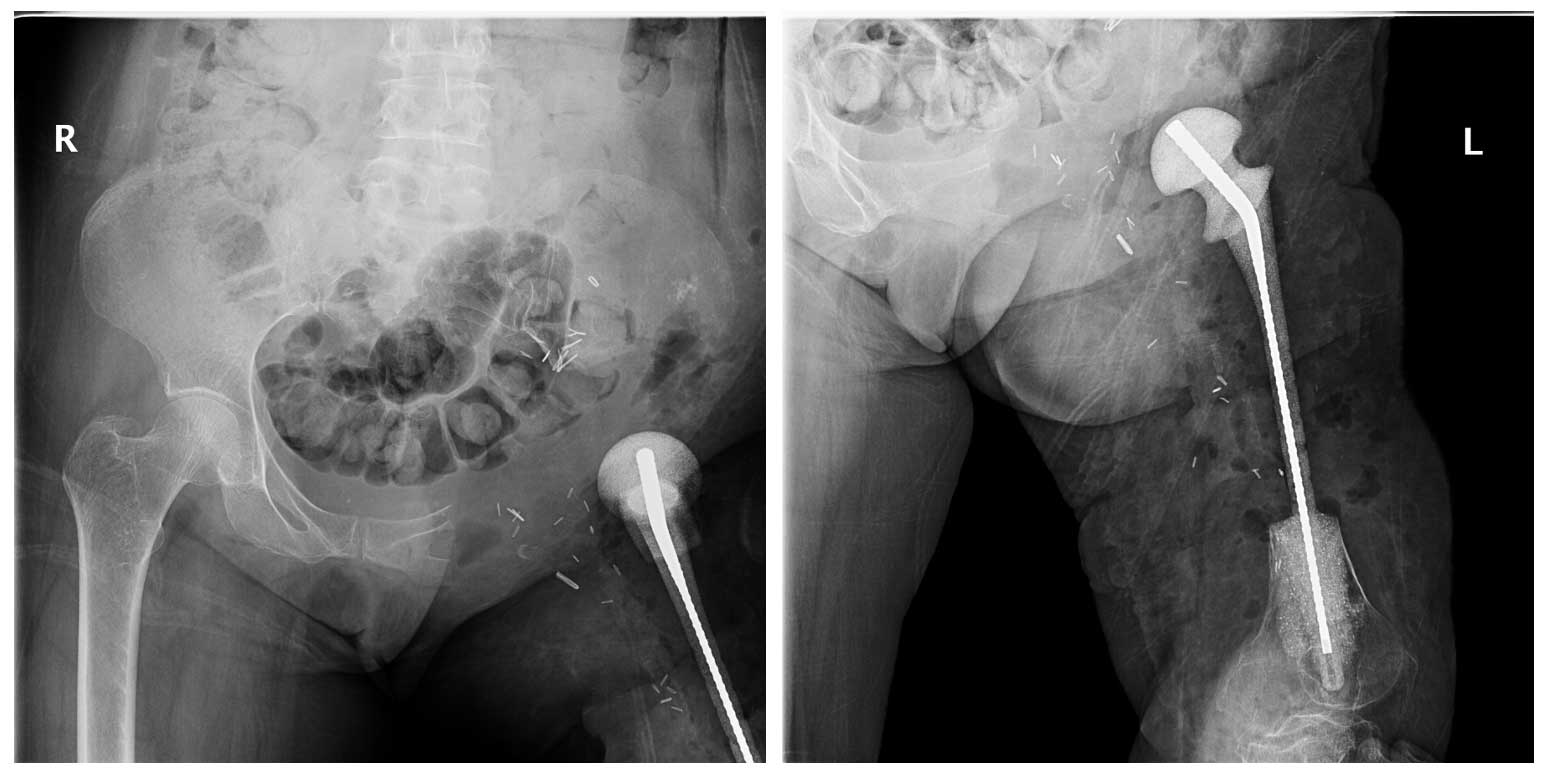

Ameliyat Öncesi: Röntgende proksimal femur yokluğu yerine spacer varlığı ve kalça ekleminde deformite ile yumuşak doku kalsifikasyonu görülmekte.